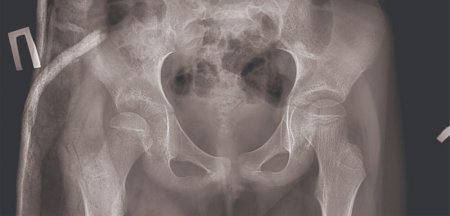

Они сообщили, что дочь жалуется на боли в районе бедра. После осмотра врачей выяснилось, что у девочки вывих кости правого бедра.

По словам родителей, девочка получила травму 17 марта после падения с алтыбакана. Ребенка лечили у народного целителя, но после были вынуждены обратиться в больницу.

Фото предоставлено пресс-службой управления здравоохранения Мангистауской области.

- На следующий день после поступления девочки врачами была проведена операция «закрытая репозиция». На данный момент ребенок чувствует себя хорошо. Пока самостоятельно ходить не может, курс лечения продолжается, - сообщили в управлении здравоохранения области.